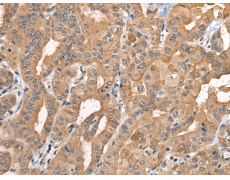

IHC positive control: |

Human thyroid cancer and human gastric cancer |